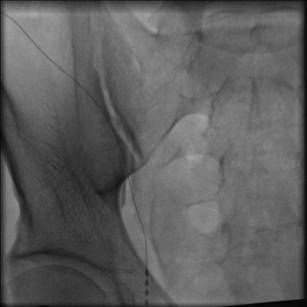

Тестовый электрод имплантируется в эпидуральное пространство чрескожно с помощью иглы Туохи под рентгеноскопическим контролем. Наружная контактная группа электрода присоединяется к портативному наружному нейростимулятору при помощи гибкого кабеля. Длительность тестового периода неоднозначна: с одной стороны более длительный период теста позволяет получить более подробную картину программирования, а с другой повышает риск инфекционных хирургических осложнений. Публикации различных авторов несут самые разнообразные сроки, однако по рекомендации компании изготовителя средний срок тестовой стимуляции не должен превышать 14 дней. За этот период пациент отвечает на вопросы наиболее комфортного режима парестезии, уменьшения болевого синдрома, изменения качества жизни и т.д.

Контроль за проведением тестового электрода

Флюороскопический контроль во время операции является необходимым условием для контроля положения иглы, уровня и места установки дистального конца электрода. Электроды чаще всего устанавливаются ростральнее неврологического уровня боли на стороне симптоматики.

После тщательной обработки операционного поля выполняется небольшой разрез в проекции остистых отростков, на фоне тщательного гемостаза отсепаровыватся паравертебрально поясничная фасция на уровне пункции эпидурального пространства (зависит от уровня неврологического проявления боли). Под углом 45• сагиттально и по направлению к средней линии под местной анестезией иглой Туохи выполняется пункция эпидурального пространства под контролем ЭОП. Также, для контроля попадания в эпидуральное пространство используется шприц низкого давления. При нахожении кончика иглы в эпидуральном пространстве исчезает ощущение резистентости в шприце, жидкость (как правило стерильная вода для иньекций) свободно проходит. Затем по игле вводится проводник для дополнительного контроля свободного проведения электрода. Далее под контролем ЭОП на нужный уровень проводятся электроды. Вид и размер элекродов подбирается в зависимости от задач, решаемых хирургом. Электрод проводится на микропроводниках, входящих в набор и облегчающих установку. Форсированное проведение электрода не рекомендуется. После установки электрода наружная контактная группа присоединяестся кабелем к программатору врача или тестовому стимулятору для подтверждения результатов тестовой стимуляции. При получении положительного результата приступают к монтажу всей системы.

Рентгенконтроль при проведении электродов